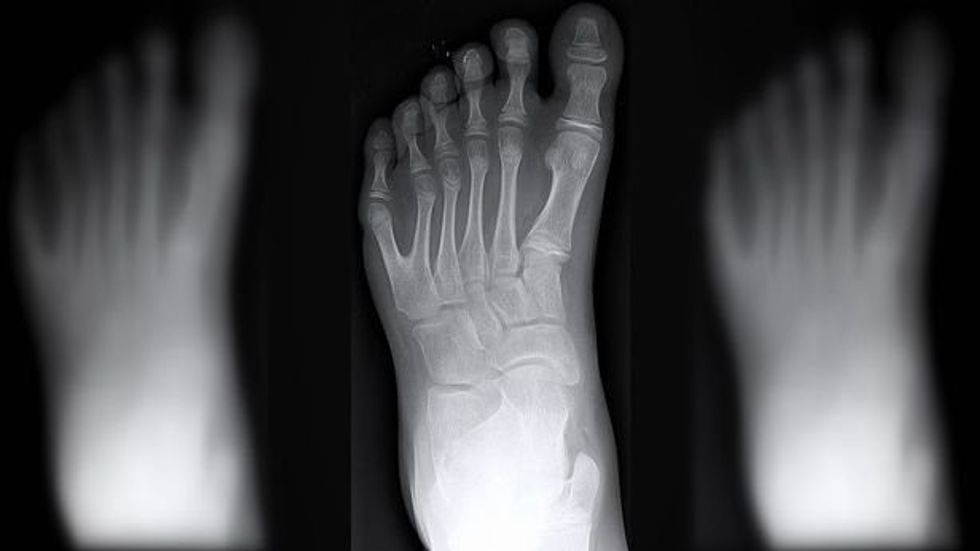

Familja 14 anëtarëshe që ka nga gjashtë gishta, i urojnë mirëseardhje në këtë botë anëtarit më të ri të familjes që ka të njëjtin sindromë gjenetike (Foto/Video)

Një familje 14 anëtarëshe ku secili prej tyre ka lindur me nga gjashtë gishta në duar e këmbë, i kanë uruar mirëseardhjen në këtë botë anëtarit më të ri të familjes, i cili ka trashëguar të njëjtin “çrregullim” gjenetik.

Ky sindrom gjenetik që i bën njerëzit të lindin me nga gjashtë gishtërinj në duar dhe këmbë quhet Polydactyly. Ajo prek një në një mijë persona, dhe për çudi në familjen De Silva ka prekur të gjithë. /Telegrafi/